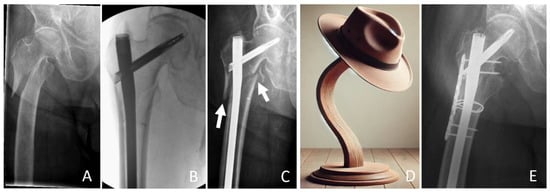

5.3. Reconstruction With or Without Additional Cables and Plates

5.5. Long Cephalomedullary Nail vs. Short Cephalomedullary Nail

- Dietze, C.; Brand, A.; Friederichs, J.; Stuby, F.; Schneidmueller, D.; von Rüden, C. Results of revision intramedullary nailing with and without auxillary plate in aseptic trochanteric and subtrochanteric nonunion. Eur. J. Trauma Emerg. Surg. 2022, 48, 1905–1911. [Google Scholar] [CrossRef] [PubMed]